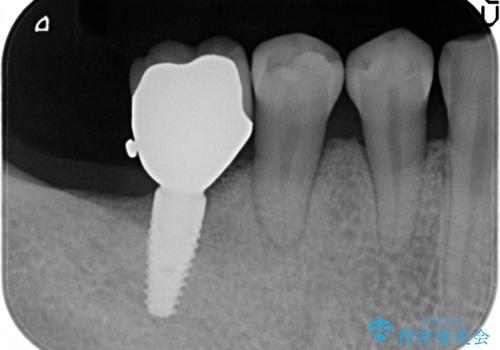

- 定期検診にて虫歯を認めた患者さんです。

患者さんの希望により、修復物の割れる心配が少ないゴールドインレーでの治療を行いました。

ゴールドインレーの場合、歯質とのすり合いを行い適合性を高めています。